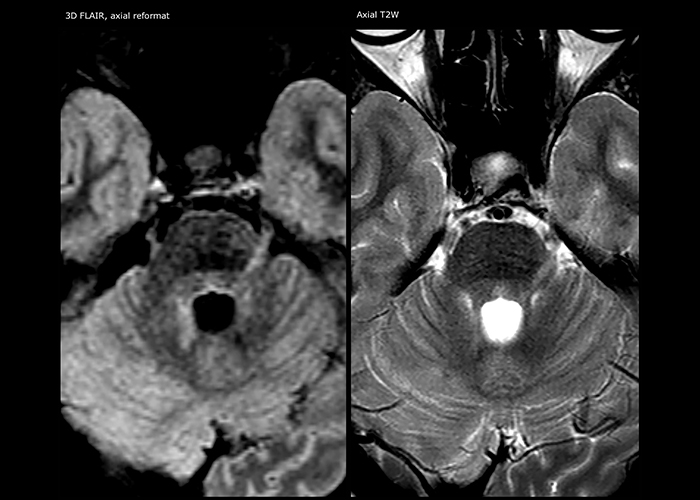

“Ingenia 3.0T provides us very good image quality with high SNR, even if we push the resolution. For example, in FLAIR images we may have an isotropic resolution of 0.9 mm. Ingenia allows us to use 3D T1 TSE with BrainView, which has a better sensitivity than 2D spin echo imaging[2] and 3D gradient echo imaging. Ingenia also provides highly reproducible exams, which is important in MS imaging so that follow-up exams at different time points are done the same way.”

For MS imaging in the brain, Dr. Savatovsky uses 3D FLAIR as the basic sequence to visualize the lesions and assess the situation and lesion load. “We count the lesions in each location to determine if the criteria of the disease are fulfilled. We use a T2-weighted sequence because our neurologists are used to it. We compare the lesion load on FLAIR with a 3D T1 post-contrast sequence to help us determine whether lesions are old or new. We typically administer the contrast before the patient enters the machine because it shortens the examination time and allows to visualize active lesions that tend to be more visible after several minutes. When a differential diagnosis is difficult, we add sequences such as susceptibility imaging, because some focal MS lesions have a small vein in the center[3].”

“For MS imaging in the spine, the basic examination includes a sagittal T2 and a post-contrast sagittal T1-weighted sequence in the whole spine. These are done in two stacks and using thin slices, for example 2 mm, without gap. As in the brain, the T2-weighted sequence visualizes the overall lesion load and helps determine if lesions are old or new. The post-contrast T1- weighted sequence helps in assessing if a lesion is new. We will sometimes add a T1 inversion recovery sequence, which has very good sensitivity, if we don’t find any lesions on T2,” Dr. Savatovsky says. “Additionally, if there is contrast enhancement outside the spine, it’s usually not MS but another kind of inflammation.”